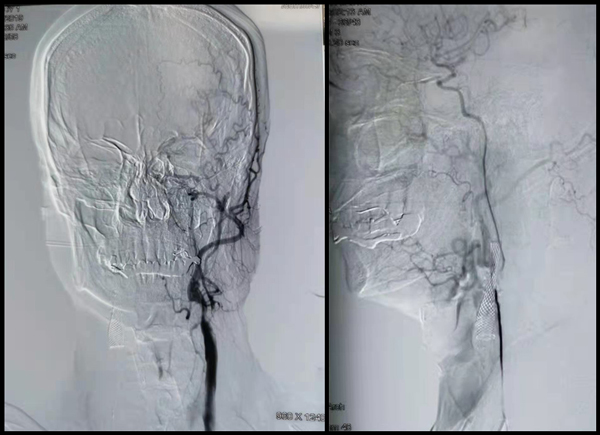

2011年患者检查出:两侧颈动脉狭窄,右侧重度狭窄,左侧更狭窄,近乎零闭塞,99%狭窄,由于导丝“无路可走”,所以北京某三甲医院给患者实施右侧颈动脉支架手术,右侧颈动脉的问题解决了,但是没有解决”最危险“的左侧颈动脉近乎闭塞的根本问题。

患者有左侧黑朦、失语现象已三个月有余。9月份张勤奕教授初次见患者时,由于患者刚突发脑梗,颅内磁共振显示:左侧存在多个梗塞在灶(左侧多个新发脑梗死),如果左侧颈动脉闭塞后,导致右侧偏瘫等,患者的性命也岌岌可危。同时,张勤奕教授还发现左侧还有一丝丝的血流可以通过颈动脉,而非完全闭塞,可以做CEA手术,难度系数非常大。由于患者是新发脑梗塞,发病一段时间以内应该以控制为主,不适宜做手术治疗,所以约定10月份进行CEA手术治疗。为患者争取时间,以防他再次脑梗,导致偏瘫、失语等严重后果,也就再也没有机会康复了。等到10月份张教授刚从美国归来以后,马上赶到鹤岗鹤矿医院为这位患者做手术,手术顺利完成。对于患者而言是至关重要、无价的。

现病史:患者于3个月前无明显原因及诱因出现头晕、一过性黑朦,未予重视。近几日病员症状逐渐加重,家属发现其症状加重,故急来医院就诊,颈部超声显示:左侧颈内血管闭塞,左侧椎动脉狭窄。

1、左侧颈内血管闭塞

2、左侧椎动脉狭窄